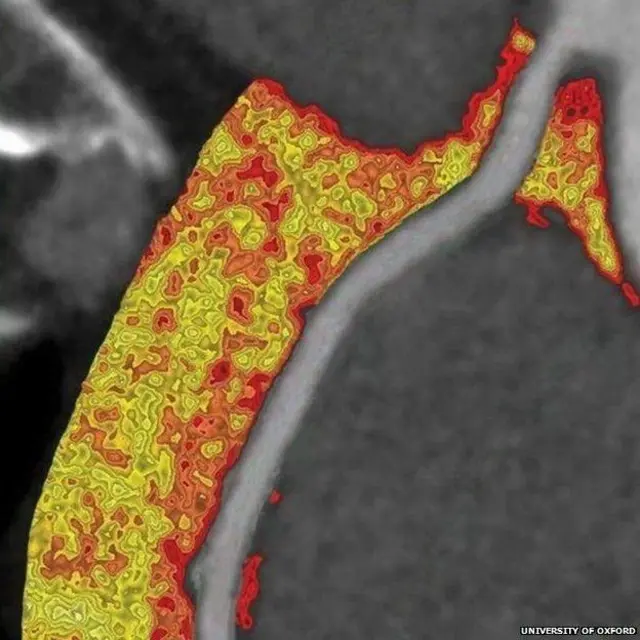

ਤਸਵੀਰ ਸਰੋਤ, UNIVERSITY OF OXFORD